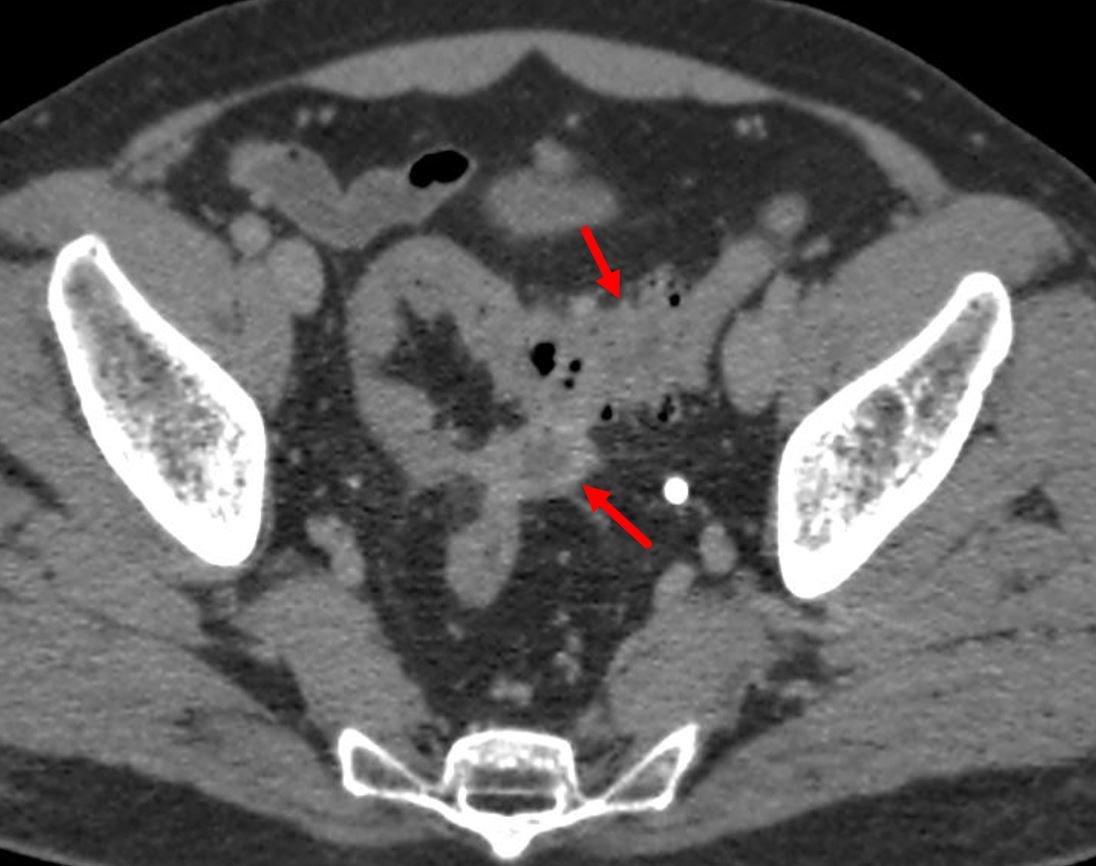

949. На представленном КТ снимке участок сигмовидной кишки с дивертикулами; стенки утолщены; в параколической клетчатке визуализируется жидкостное округлое образование диаметром 2,5 см с толстыми стенками, что по классификации осложнений дивертикулярной болезни соответствует картине